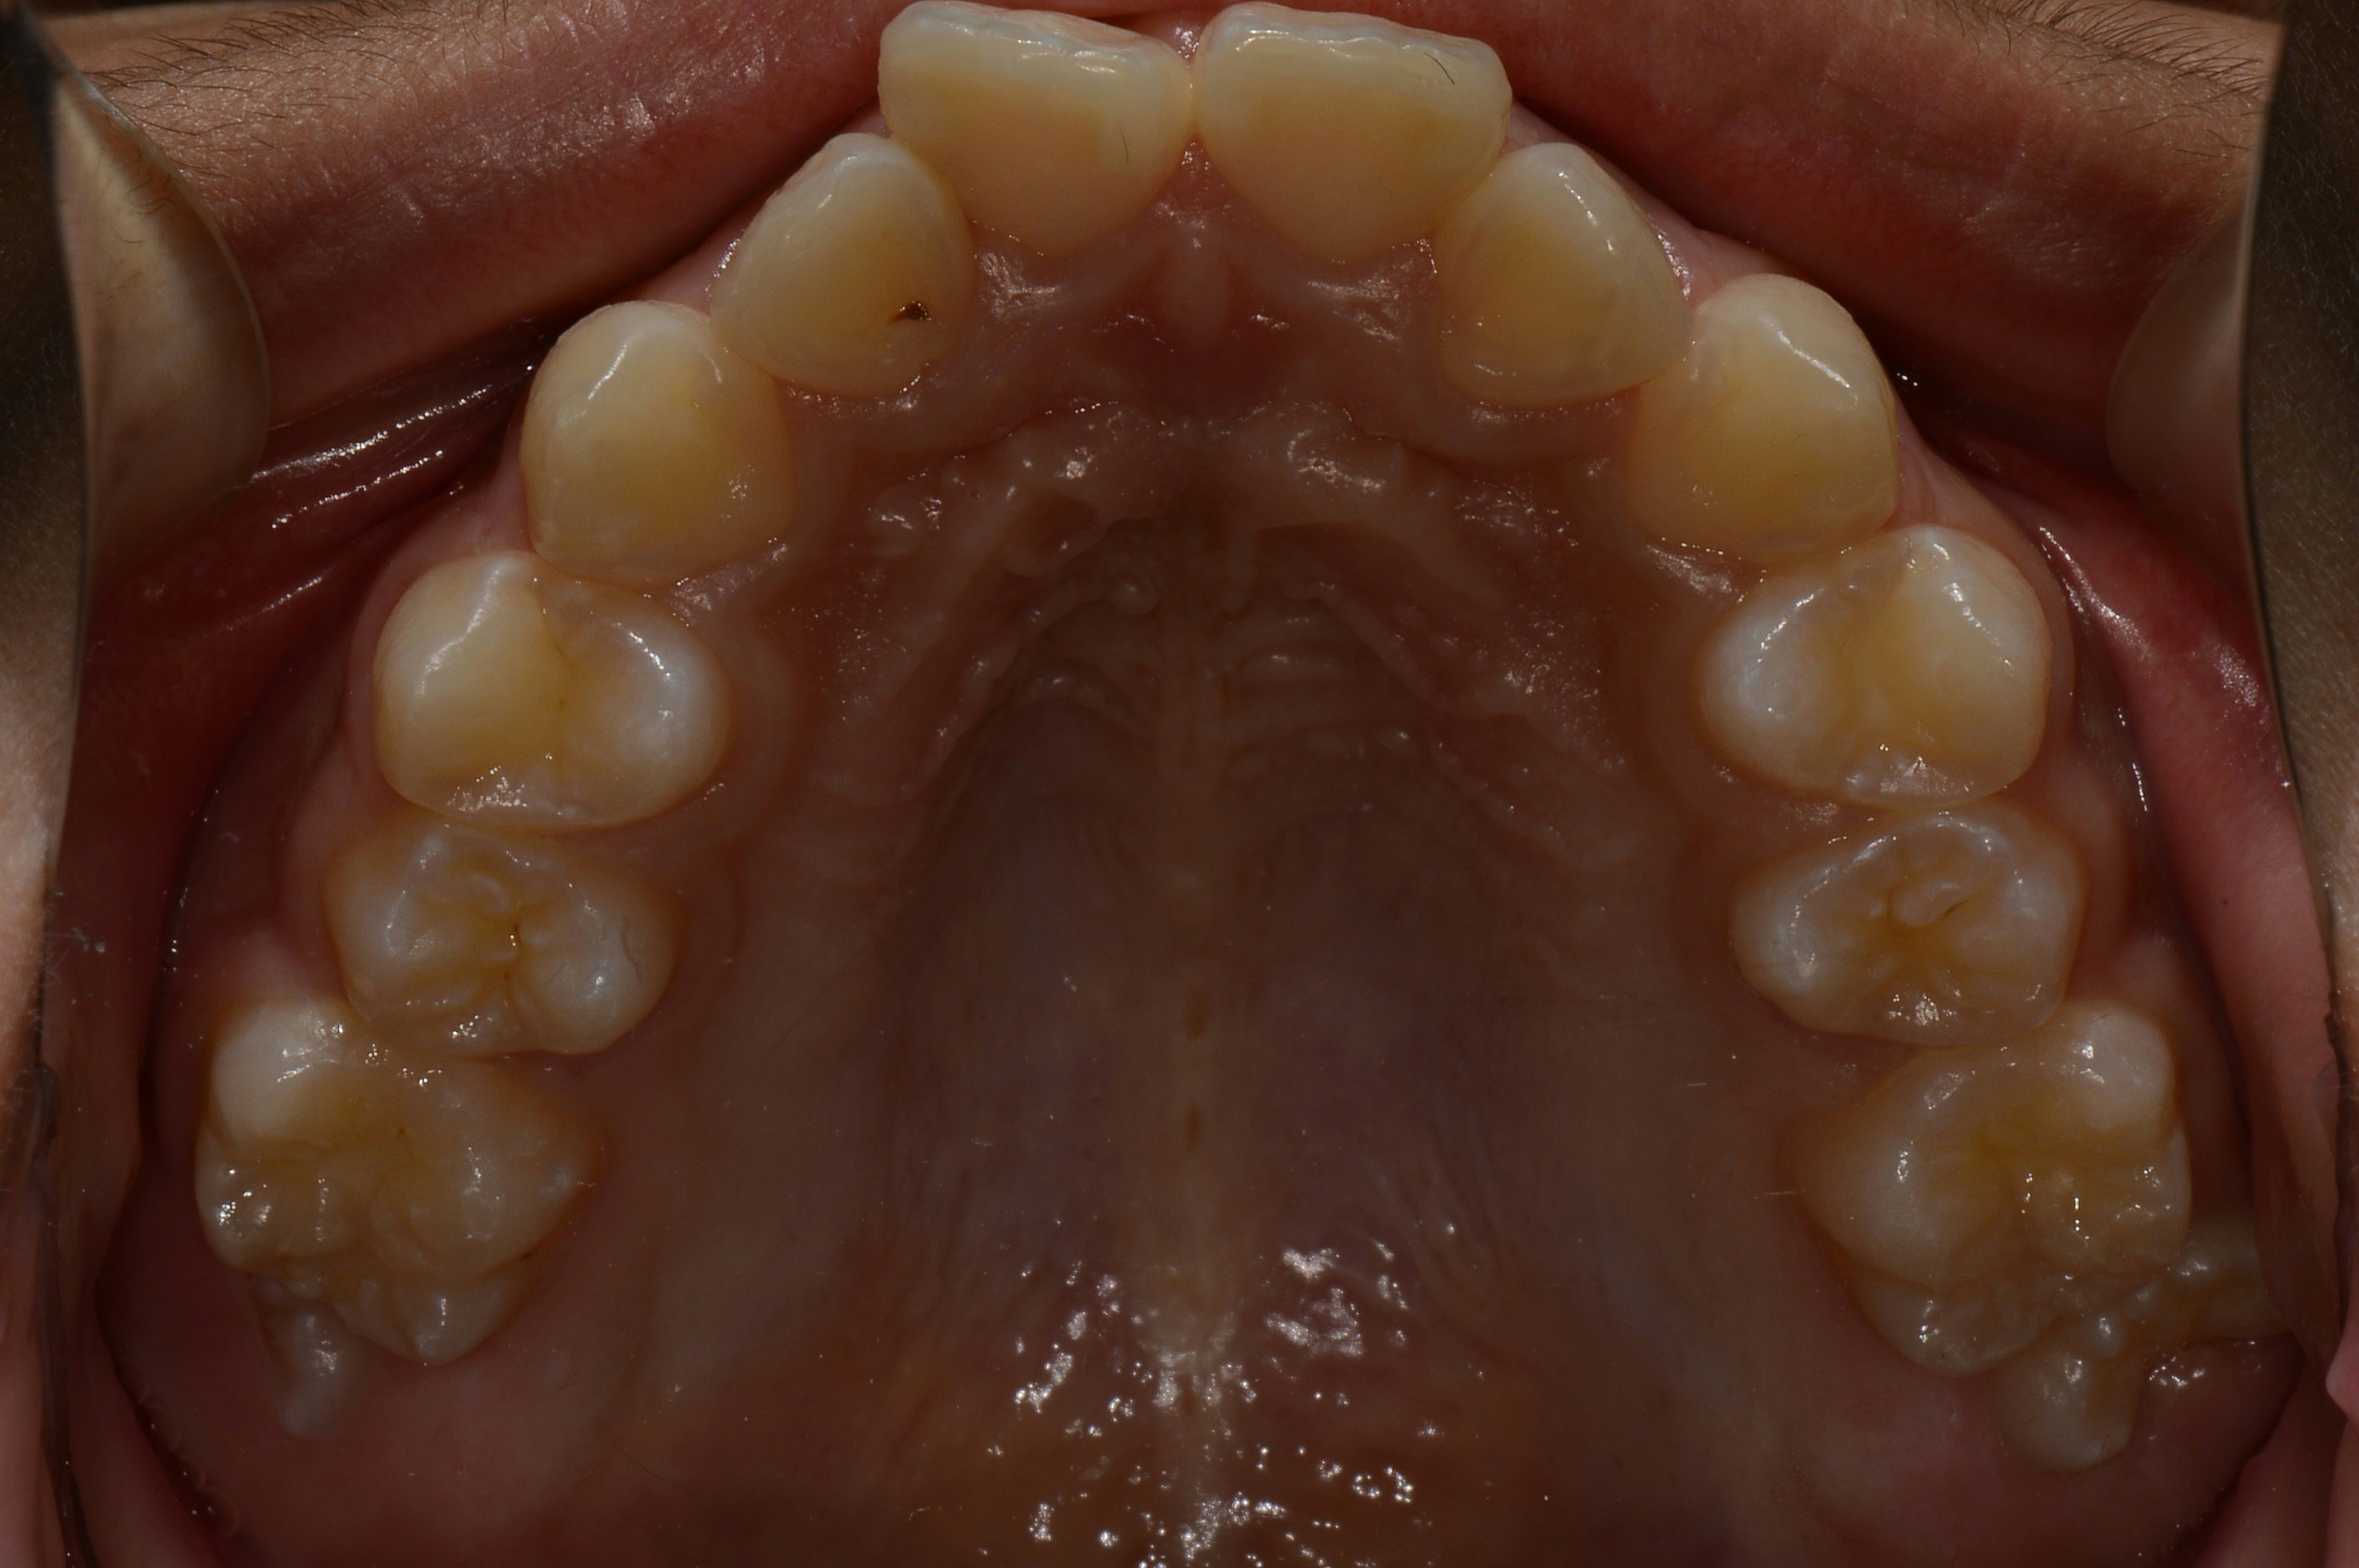

치료 전 사진입니다.